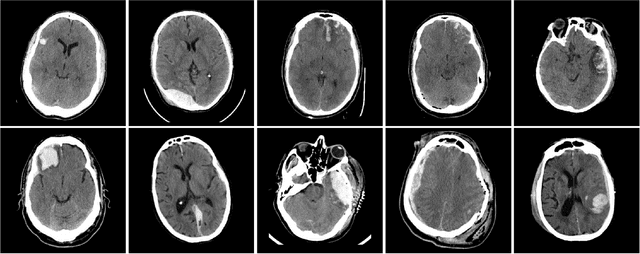

Machine learning models are becoming commonplace in the domain of medical imaging, and with these methods comes an ever-increasing need for more data. However, to preserve patient anonymity it is frequently impractical or prohibited to transfer protected health information (PHI) between institutions. Additionally, due to the nature of some studies, there may not be a large public dataset available on which to train models. To address this conundrum, we analyze the efficacy of transferring the model itself in lieu of data between different sites. By doing so we accomplish two goals: 1) the model gains access to training on a larger dataset that it could not normally obtain and 2) the model better generalizes, having trained on data from separate locations. In this paper, we implement multi-site learning with disparate datasets from the National Institutes of Health (NIH) and Vanderbilt University Medical Center (VUMC) without compromising PHI. Three neural networks are trained to convergence on a computed tomography (CT) brain hematoma segmentation task: one only with NIH data,one only with VUMC data, and one multi-site model alternating between NIH and VUMC data. Resultant lesion masks with the multi-site model attain an average Dice similarity coefficient of 0.64 and the automatically segmented hematoma volumes correlate to those done manually with a Pearson correlation coefficient of 0.87,corresponding to an 8% and 5% improvement, respectively, over the single-site model counterparts.